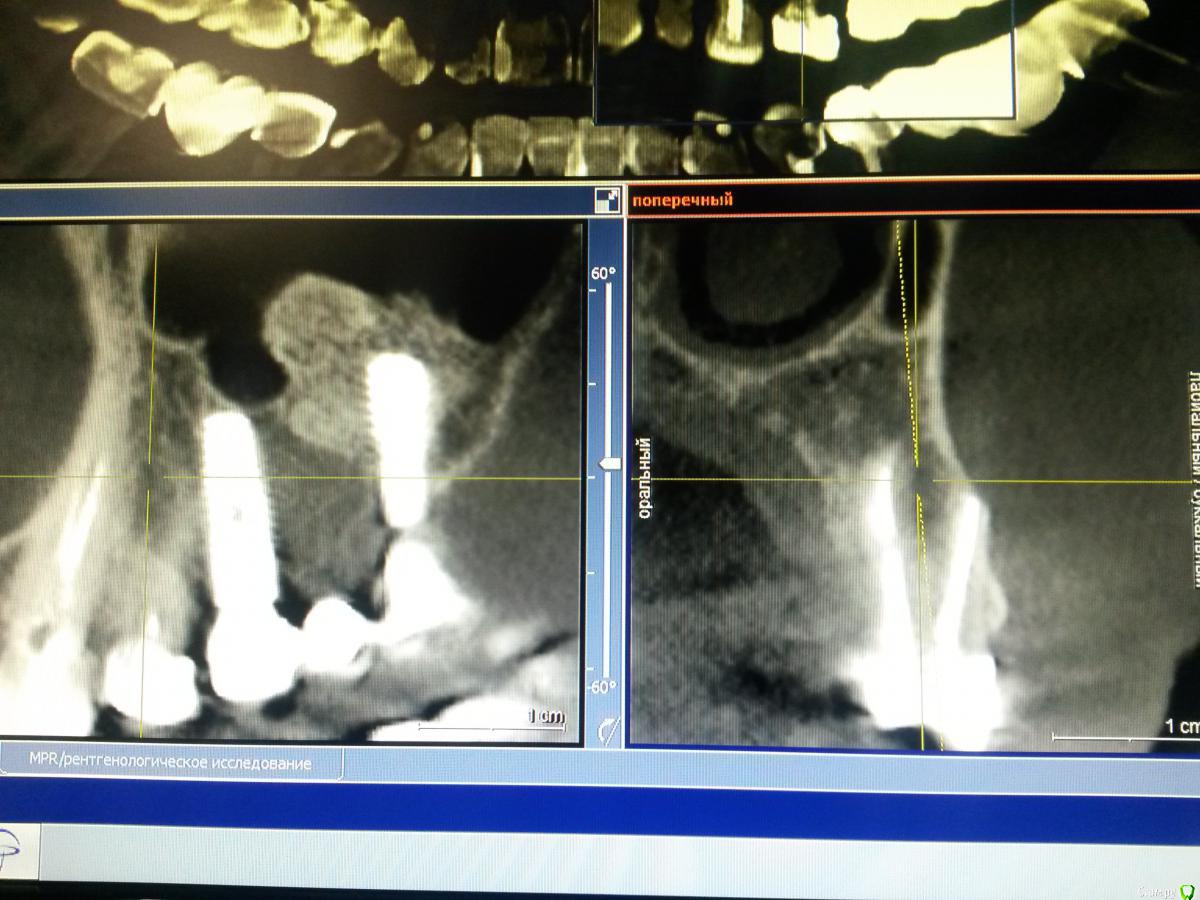

Nazim_NV86 Опубликовано 2 апреля, 2015 Поделиться Опубликовано 2 апреля, 2015 Оперирована 2г назад. Через полгода отпротезирована. Есть жалобы на периодическое жжение и нытьё. С периодами ремиссии и обострения. Со стороны СОПР всё в норме. Перкуссия отриц. Пальпаторно она сама не может понять где как и что. Во время операции ампутировал торчащий апекс 2.4. Была у 2 невропатологов. Бесполезно. Ссылка на комментарий

Nazim_NV86 Опубликовано 2 апреля, 2015 Автор Поделиться Опубликовано 2 апреля, 2015 Импланты Osstem Gs3. Bio-oss. Bio-gide. Ссылка на комментарий

Nazim_NV86 Опубликовано 3 апреля, 2015 Автор Поделиться Опубликовано 3 апреля, 2015 Подойдет Rg перед имплантацией.Когда появились жалобы? Связывает с чем-нибудь?Жалобы появились через месяц после операции. Вначале всё связывали с постоперационным синдромом. До операции КТ не было. Только ОПТГ. До ближайшего томографа 200км. Теперь уже у нас в городе их 3 шт. Этот Sirona. Ссылка на комментарий